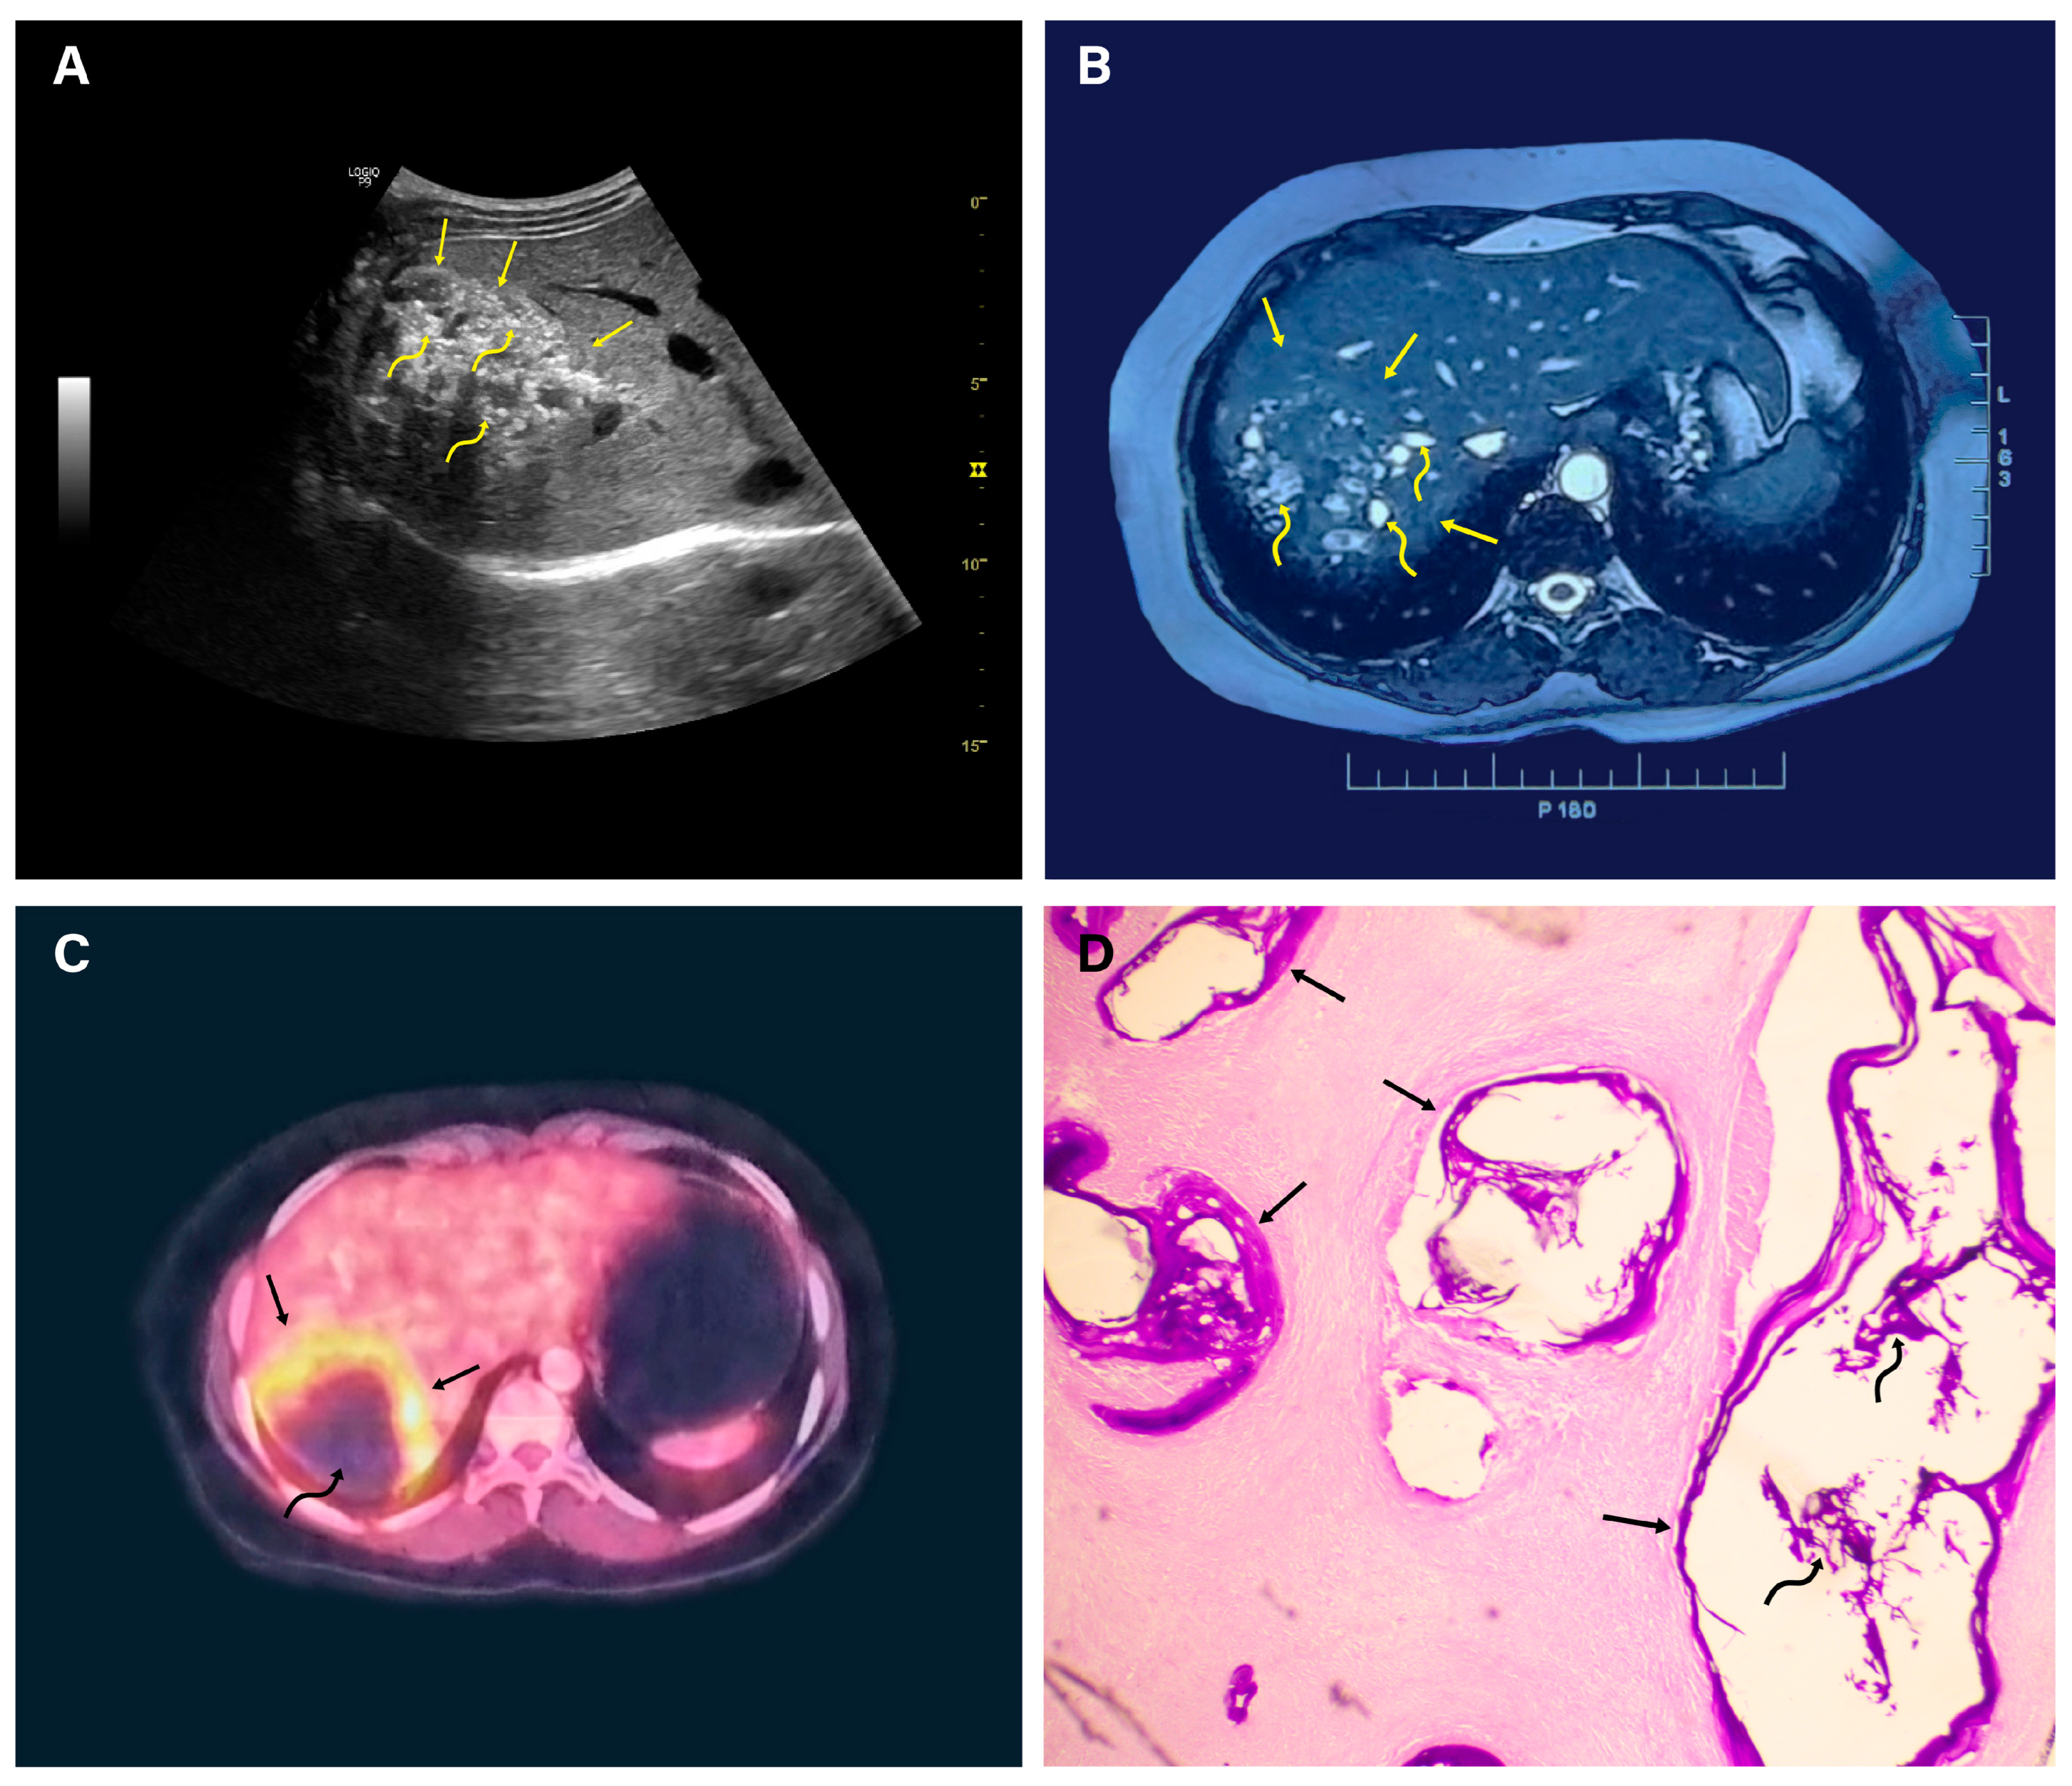

- Parry, A.H.; Wani, A.H.; Feroz, I. The spectrum of multimodality imaging findings in hepatic alveolar echinococcosis and the potential role of diffusion-weighted imaging in its characterisation. Pol. J. Radiol. 2020, 85, e613–e623. [Google Scholar] [CrossRef] [PubMed]

- Bulakçı, M.; Kartal, M.G.; Yılmaz, S.; Yılmaz, E.; Yılmaz, R.; Şahin, D.; Aşık, M.; Erol, O.B. Multimodality imaging in diagnosis and management of alveolar echinococcosis: An update. Diagn. Interv. Radiol. 2016, 22, 247–256. [Google Scholar] [CrossRef]

- Kodama, Y.; Fujita, N.; Shimizu, T.; Endo, H.; Nambu, T.; Sato, N.; Todo, S.; Miyasaka, K. Alveolar echinococcosis: MR findings in the liver. Radiology 2003, 228, 172–177. [Google Scholar] [CrossRef] [PubMed]

- Brumpt, É.; Liu, W.; Graeter, T.; Calame, P.; Rong, S.; Jiang, Y.; Li, W.; Bao, H.; Delabrousse, É. Kodama-XUUB: An informative classification for alveolar echinococcosis hepatic lesions on magnetic resonance imaging. Parasite 2021, 28, 66. [Google Scholar] [CrossRef] [PubMed]

- Arena, V.; Skanjeti, A.; Casoni, R.; Douroukas, A.; Pelosi, E. Dual-phase FDG-PET: Delayed acquisition improves hepatic detectability of pathological uptake. Radiol. Med. 2008, 113, 875–886. [Google Scholar] [CrossRef]

- Caoduro, C.; Porot, C.; Vuitton, D.A.; Bresson-Hadni, S.; Grenouillet, F.; Richou, C.; Boulahdour, H.; Blagosklonov, O. The role of delayed 18F-FDG PET imaging in the follow-up of patients with alveolar echinococcosis. J. Nucl. Med. 2013, 54, 358–363. [Google Scholar] [CrossRef]